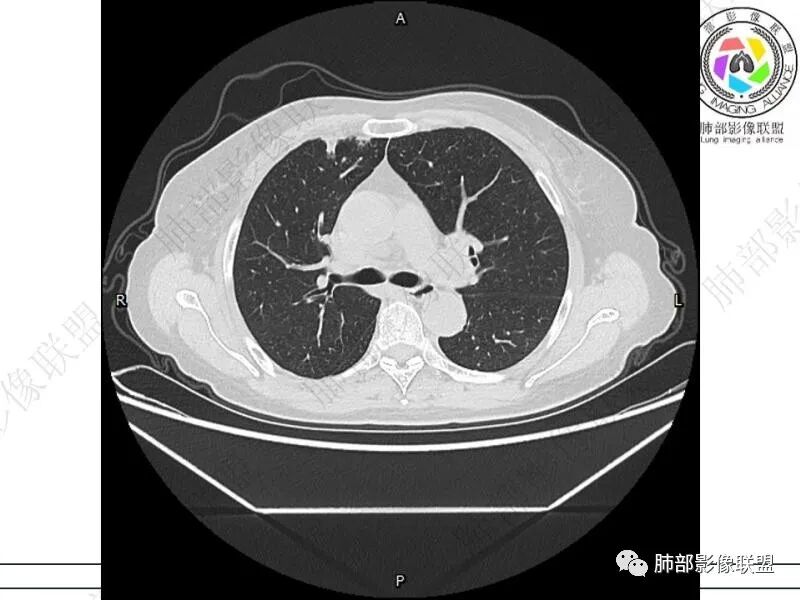

摘星空竹子:两肺胸膜下多发实性结节、磨玻璃影及实变影,短期复查病变有所进展,考虑感染性病变,隐球菌可能,患者有右半结肠癌手术史,转移不能除外。

简单:双肺及胸膜下多发小结节,双下肺胸膜下宽基底团块影,短期内病灶进展考虑炎性病变,隐球?患者ca术后,双肺小结节随诊除外转移

丽:双肺下叶胸膜下多发片状高密度影,边缘模糊不清,内可见支气管穿行,病变长轴平行于胸膜,考虑感染性病变,隐球菌

媛:肠癌术后,免疫力低下。两肺胸膜下结节及实变影,实变影长轴平行于胸膜,密度均匀,边界偏清,周围有晕征,短期复查进展,虽隐球菌荚膜抗原检测阴性,还是考虑隐球菌,鉴别OP

谢加平:结肠癌术后史,两肺胸膜下多发结节及斑块实变病灶,实边边界平直征(亚急性和慢性病变过程),双肺下叶后基底段胸膜下为甚,与胸膜平行特点,见支气管充气征,边缘模糊的GG0,首诊2022年11月18日肺部CT,与治疗11月28日对比,病灶未吸收,双肺下叶胸膜下病灶有侧向融合特点,综合分析符合炎性肉芽肿,隐球菌感染。

老年女性,结肠癌术后。两下肺胸膜下为主片状实变,右下肺短期复查融合且病灶长轴平行于胸膜,实变内可见支气管充气征,边缘磨玻璃晕,另两肺内胸膜下散在数枚小结节状、楔形实性灶。考虑感染性病变,隐球菌可能,鉴别肺转移。

2.影像特征:双肺胸膜下多发实性结节、磨玻璃影及实变影,胸膜下优势分布、晕征、胸膜下脂肪间隙存在,部分病灶边界平直征,有侧向融合趋势。